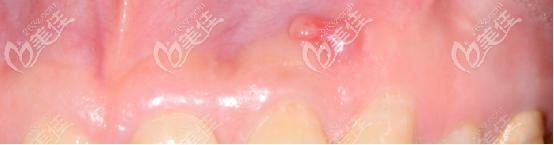

(這個膿包并沒有消失)

第二次終于找到引發(fā)小膿包真正的元兇: